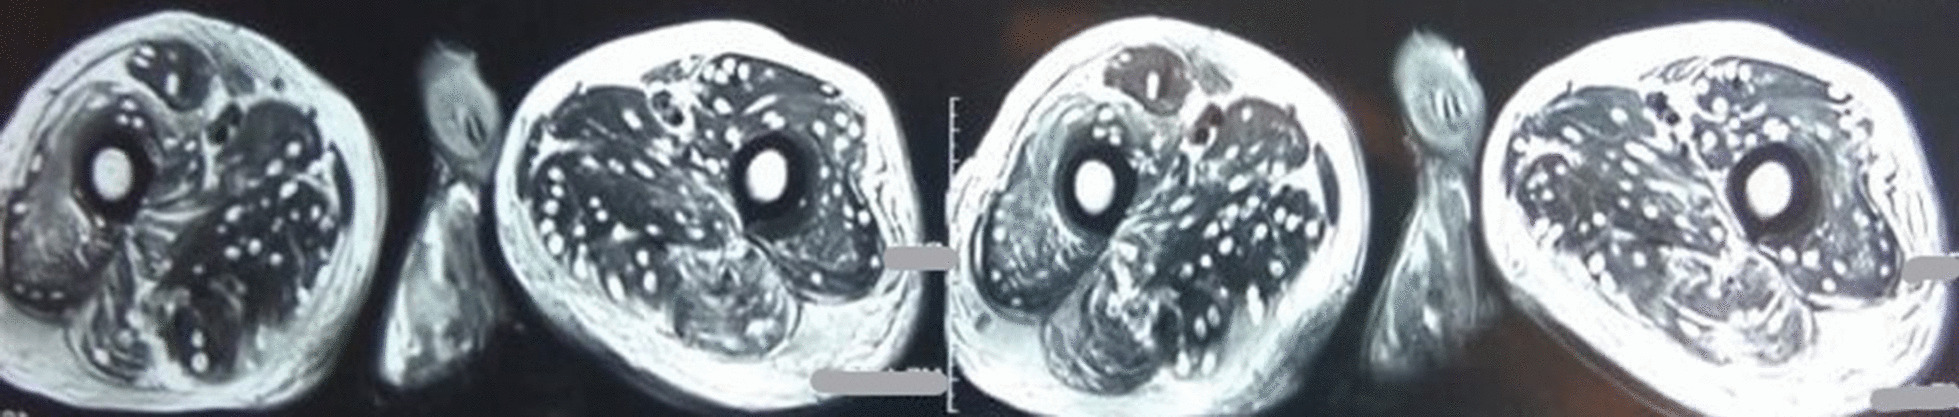

Fig. 4.

Magnetic Resonance Imaging of thigh muscles showing numerous cysticerci